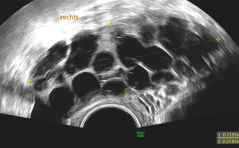

Der Transport durch den Eileiter: Wie funktioniert er eigentlich?

Und: Eine mögliche Erklärung für die Entstehung einer Eileiterschwan-gerschaft? / Ovarialkarzinom bei einem Transgender-Mann: Ein komple-xer Fall / FGM/FGC in der Schweiz – wie hoch ist die ...